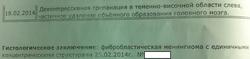

Начало вот здесь http://www.radiomed.ru/cases/kt-gms-obemnoe-obrazovanie-levoi-gemisfery-bolshogo-mozga-vnutrizheludochkovaya-meningioma. Пациент оперирован (меня сначала дезинформировали по поводу операции), перед операцией состояние ухудшилось, возникла правосторонняя гемиплегия, которая осталась и после декомпрессии. МРТ, КТ снимки и выписку предоставила супруга пациента, снимал на iphone, простите за качество, дисков с исследованиями не записывали. Надеюсь вопрос по данному случаю исчерпан.

А вот и "ягодка".

Мне видится так. Иначе в данной локализации просто неоткуда расти оболочечной опухоли. На контрольной КТ, после декомпрессии, когда срединные структуры стали действительно срединны, правое обызвествленное сосудистое сплетение видно отчетливо, а левое, где оно? Ведь если бы образование компремировало, то после операции, когда часть мозга пролабировало в трепанационное отверстие мы бы увидели и левое сосудистое сплетение, но оно интимно связано с образованием и даже "потянулось" за ним в сторону декомпрессионного отверстия, потому что это и есть "росток" откуда выросла опухоль.